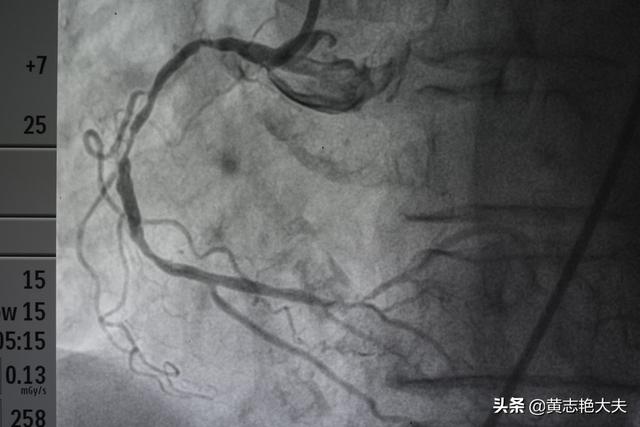

- 造影剤は冠動脈を "照らす":人体の冠動脈は比較的小さく、冠動脈の主幹はわずか5、6ミリ、太い枝の一部は2、3ミリ程度、残りはさらに細い枝で、これらの血管は周囲の組織とつながっており、その手前は骨や筋肉などで覆われている。そこで、冠動脈造影を行う際には、先ほどのカテーテルの中から造影剤を注入し、冠動脈を造影剤で満たします。造影剤はX線不透過性の薬剤で、冠動脈造影の際に冠動脈を "明るく "照らし、冠動脈の分布、大きさ、狭窄や閉塞の有無をはっきり見ることができる。

- DSA(Digital Subtraction Angiography)とは血管を撮影するカメラである:先に述べた冠動脈の写真を撮るための装置がDSAであるが、実はこれもX線検査の一種であり、造影剤を注入しながら様々な冠動脈を多角的に、まさに360度の死角とも言える角度から写真や動画を撮影・記録することができ、これらの写真や動画はCD-ROMに預けることができるので保存や解析が容易である。冠動脈造影が冠動脈疾患を診断するためのゴールドスタンダードであるのは、冠動脈造影がこれほど鮮明な写真やビデオを撮ることができるからである。

冠動脈造影検査は、大腿動脈の位置から針を刺し、冠動脈の位置までチューブを通し、ヨード造影剤を打ち込んで冠動脈を映し出し、冠動脈の先天性疾患、アテローム性動脈硬化症、動脈瘤、動脈奇形などを診断するもので、その多くは内腔の狭窄をもたらすアテローム性動脈硬化症である。狭窄の程度を評価することができ、心筋梗塞を伴う重度の狭窄の場合は、治療目的で狭窄した内腔を広げて血流を回復させるためにステントを直接挿入することができる。

心血管造影は冠動脈造影を指し、一般的なプロセスは、最初の検査者の橈骨動脈または大腿動脈で小さな開口部をカットし、細いカテーテルは、切開から挿入される動脈の方向に沿って冠動脈に深くされており、その後、冠動脈画像は、冠動脈疾患とその枝の冠動脈疾患の部位と程度の狭窄について明確にすることができるように、造影剤に注入され、冠動脈疾患の診断です。「ゴールドスタンダード」である。以下、3つの問題を合わせて理解する: